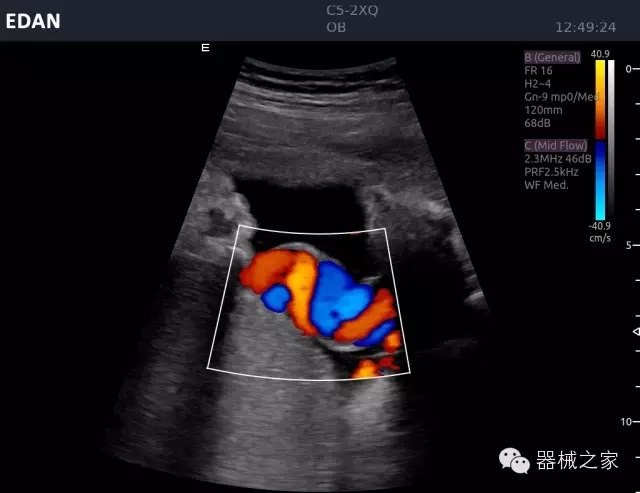

臨床圖片賞析

睪丸低速血流

臍帶血流